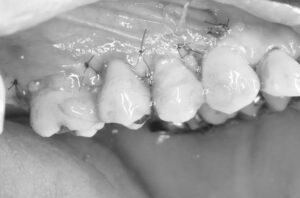

治療前後です。

外科後2年の歯肉の状態です。

歯肉が下がっておらず、良好な状態です。

術前と術後1年半の比較です。

歯肉退縮も最小限で良好な歯周組織を維持しています。